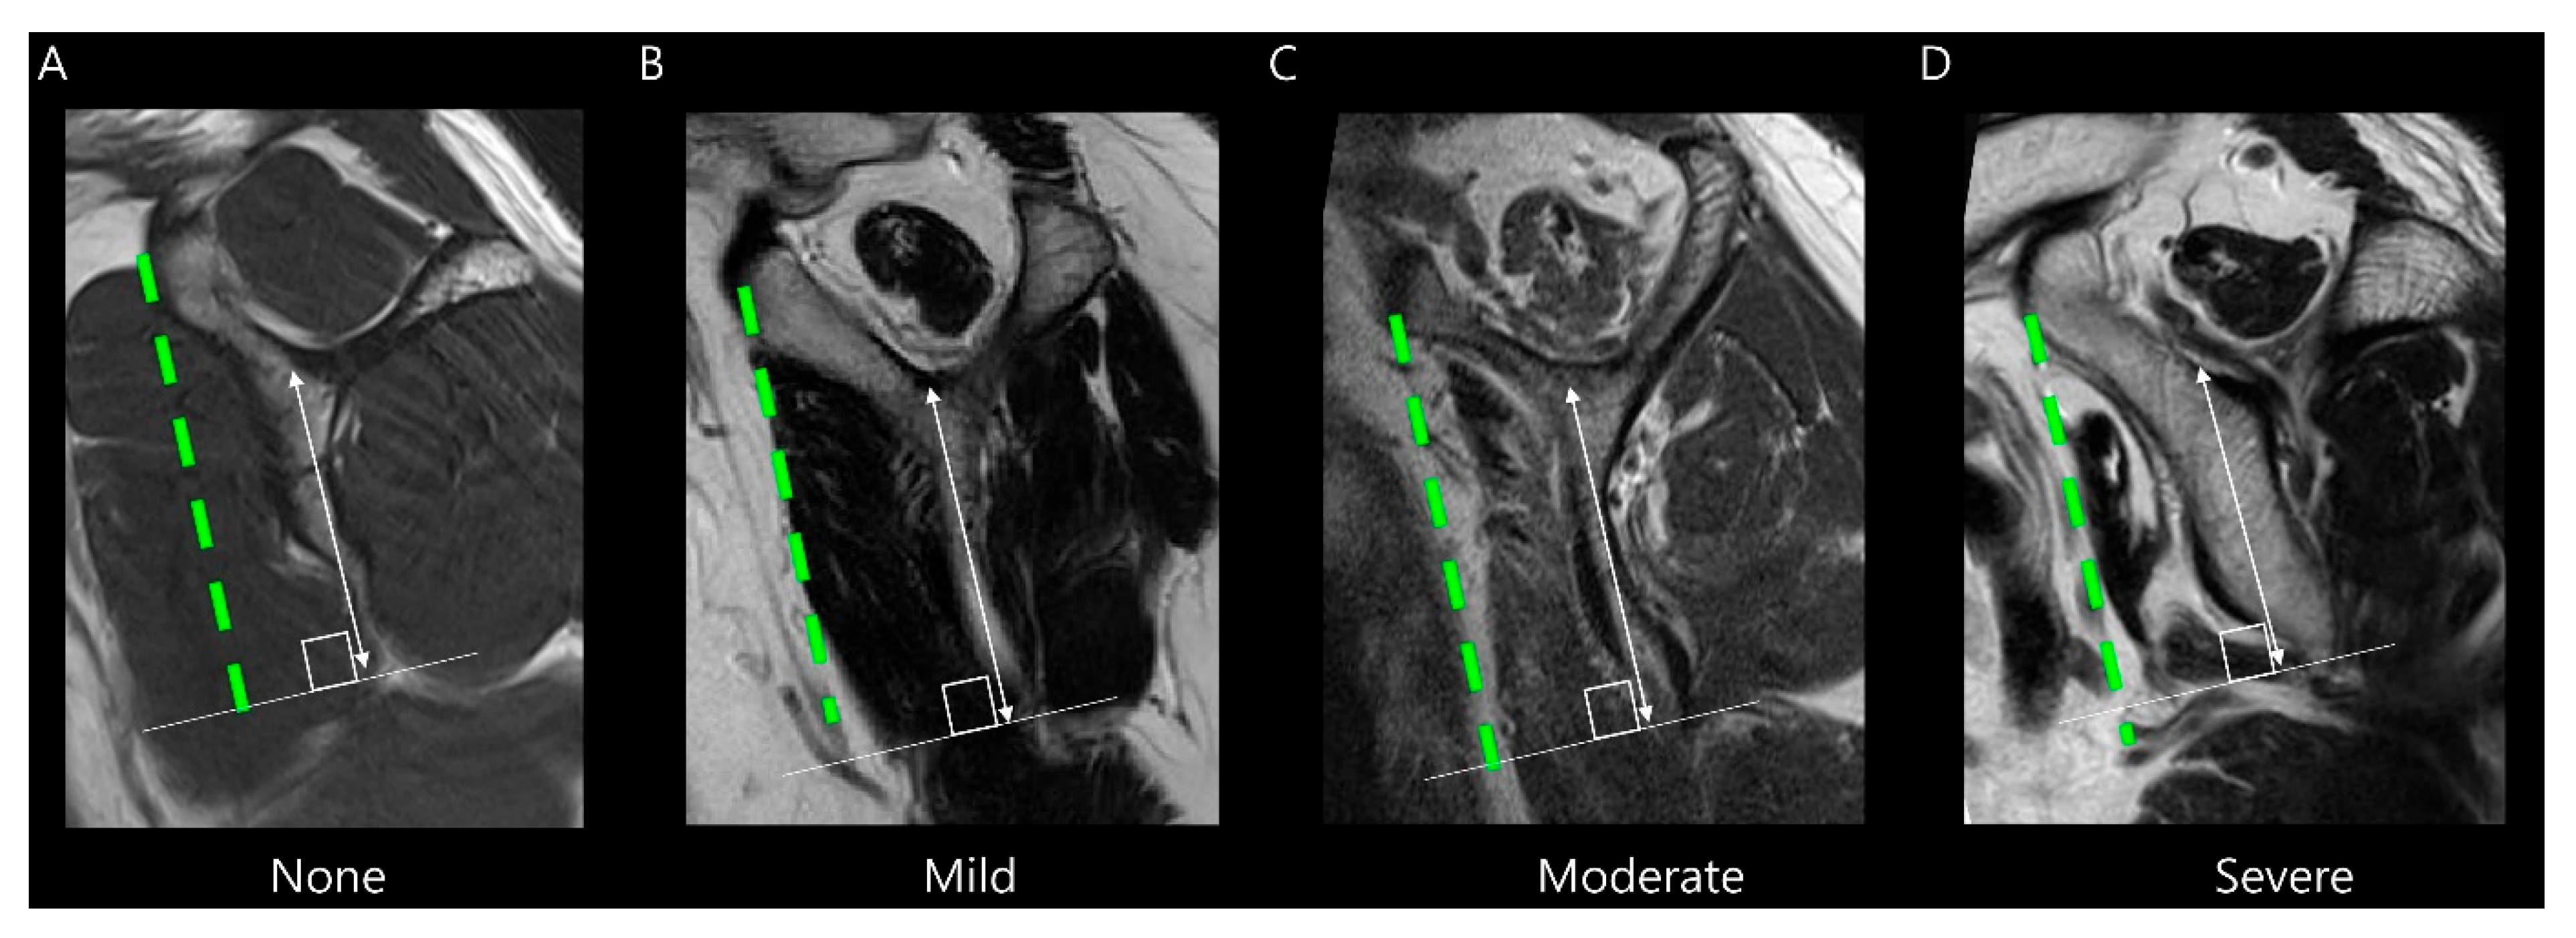

Fatty infiltration for the subscapularis muscle was assessed using the modified Goutallier method proposed by Yoon et al. [14]. In this system, the degree of fatty infiltration is graded separately for the upper and lower portions of the muscle (Table 2). Representative MRI examples of each modified Goutallier grade are presented in Figure 5. For statistical analysis, we categorized fatty infiltration into two categories: grade 0–1 and grade 2–3. No cases in this study showed grade 4 or higher fatty infiltration.

Figure 5.

Evaluation of subscapularis muscle fatty infiltration on T2-weighted oblique sagittal images according to the modified Goutallier method [14]: (A) Grade 0: no fat. (B) Grade 1: some fatty streaks. (C) Grade 2: less fat than muscle in the upper half of the muscle. (D) Grade 3: more fat than muscle in the upper half of the muscle, with normal or fatty streaks in the lower half of the muscle. (E) Grade 4: more fat than muscle in the upper half of the muscle, with less fat than muscle in the lower half of the muscle. (F) Grade 5: more fat than muscle in the upper and lower halves of the muscle.